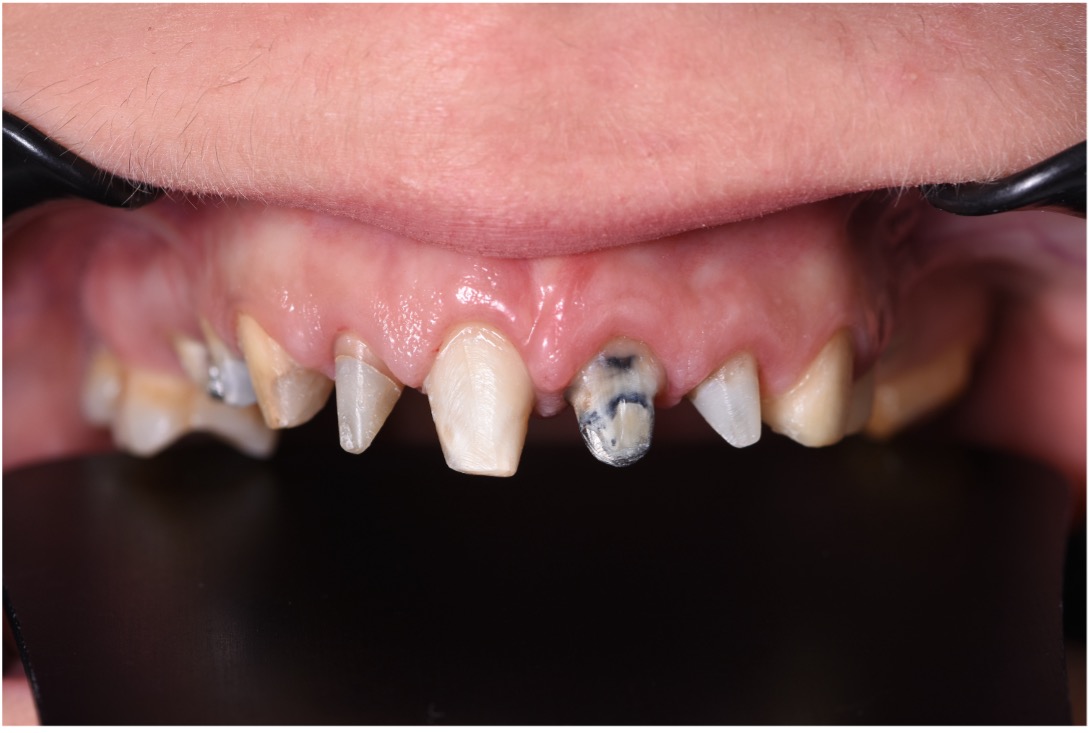

• Chief Complaint: Gummy Smile and Old Crowns

• Initial Diagnosis: Excessive Gummy Smile and Discolored old crowns

Step 1: Diagnostic Assessment and Smile Design The treatment began with a comprehensive evaluation of the patient’s smile using facially guided diagnostics. The Facial Flow Concept was employed to assess the relationship between the patient's facial structure, lips, smile arc, and gingival display. SmileFy software was utilized to generate a 2D digital smile simulation.

This visualization allowed both the clinical team and the patient to preview the planned esthetic outcome. It also provided a platform for mutual understanding and expectation management, forming a blueprint for all subsequent steps.